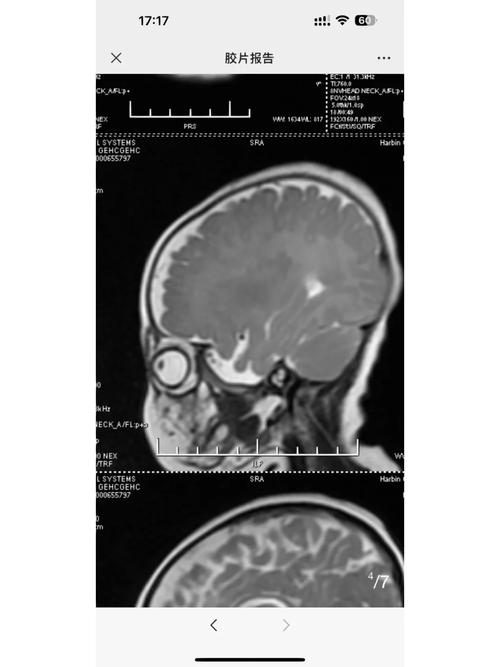

- CT表现:脑白质,特别是侧脑室周围的白质,会出现弥漫性或片状的密度降低,严重时,脑沟可能变浅,脑室可能扩大,这是脑水肿的表现。

- 其他检查:是否有头颅B超(对新生儿更常用,无辐射)、MRI(磁共振,对脑白质显示更清晰)的结果?这些比CT更有价值。

- CT vs. MRI:对于新生儿脑部评估,MRI是金标准,CT虽然快速、方便,但对脑白质的细微结构和早期病变的分辨能力不如MRI,且有辐射,医生可能会建议在宝宝情况稳定后,做一个头颅MRI来更准确地评估脑损伤的范围和性质。